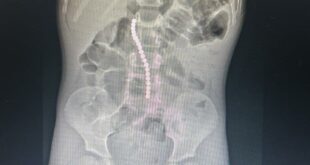

Дәрігерлер 20 магнит жұтып қойған баланы аман алып қалды

14.04.2026. Abai.Media. «СМУ Университеттік госпиталі»КеАҚ жедел түрде жағдайы күрт нашарлаған бала жеткізілді. Анықталғандай, кішкентай науқас …